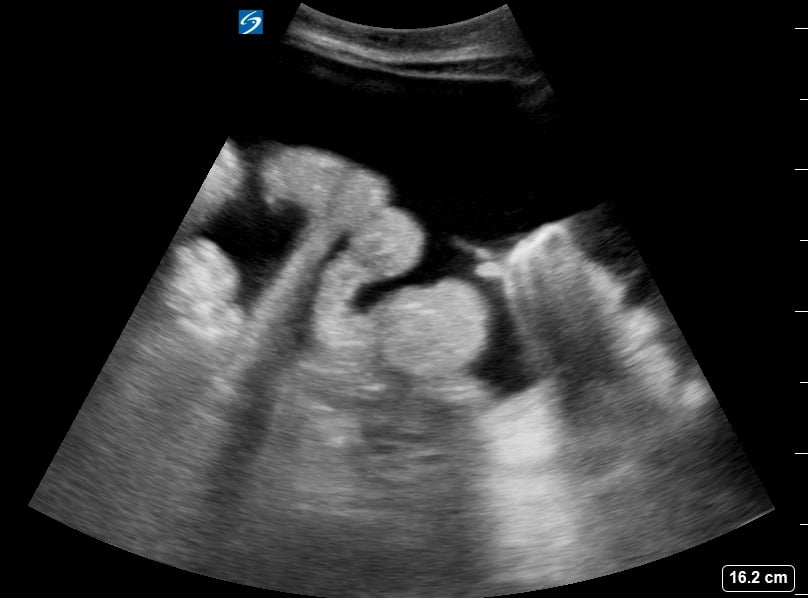

Ascites refers to the abnormal accumulation of fluid within the peritoneal cavity, the space surrounding abdominal organs. In medical imaging, particularly with ultrasound, ascites presents as an anechoic (black) or hypoechoic (dark) fluid collection, often outlining bowel loops or organs. This condition is a key indicator of underlying pathologies such as liver cirrhosis, heart failure, kidney disease, or certain cancers, requiring accurate diagnosis for proper patient management.

Ultrasound is a crucial tool for detecting and quantifying abdominal ascites due to its real-time imaging capabilities and portability. Sonographers can effectively visualize even small amounts of fluid, aiding in diagnostic assessments and guiding therapeutic procedures like paracentesis. Understanding ascites on ultrasound is essential for precise medical diagnosis and optimizing patient care in abdominal evaluations.